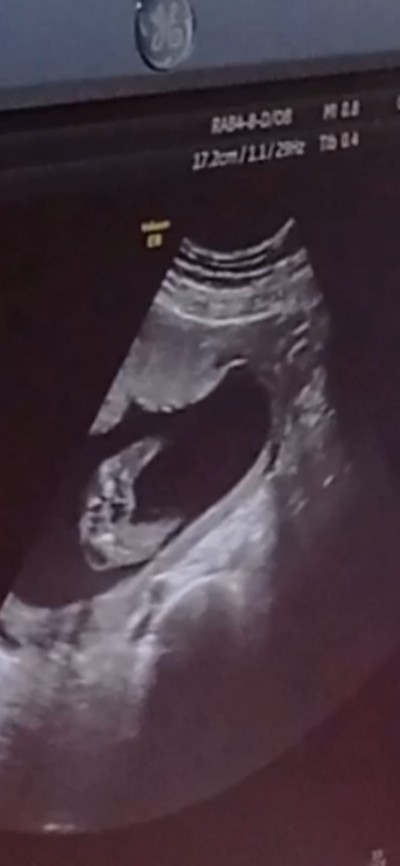

image

11. Haftadan bu yana açık sağolsun ☺️ 11 de kız kesin dedi 29 haftalığız değişmedi tamamen bebisle alakalı ☺️

(395 puan)

Bana da 13 te kız dedi 11 de de kız gibi demişti bakalım 15 i geçtik ne diyecek :)